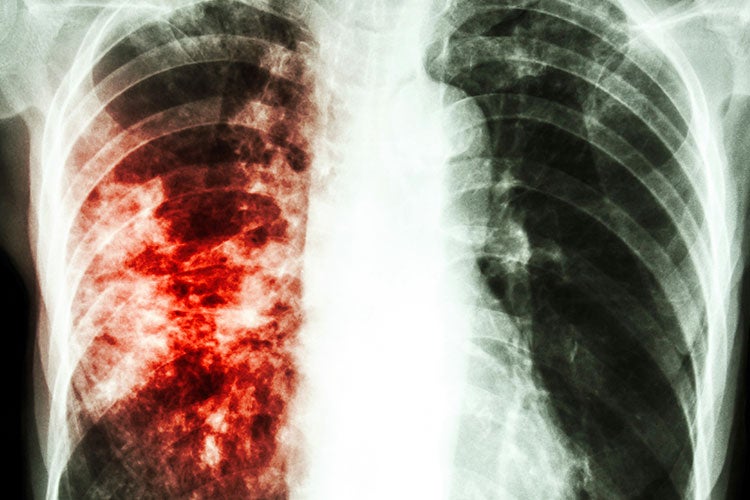

Симптомы туберкулеза: Как распознать и что делать

Раздел: Визуальные уроки